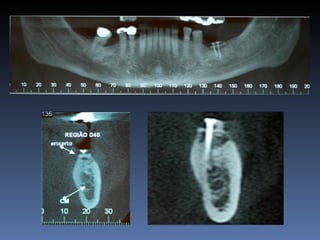

BOX 5

Neide Sanches Mansur

Idade – 69 anos

Sexo – Feminino

Raça – Caucasiana

ASA – II

Data- 28-04-2012

Diagnóstico: Desdentada parcial

posterior da mandibula,

zona 4.3,4.4,4.5,4.6.

Plano de tratamento: Instalação de 4 implantes endo-

ósseos para reabilitação protética fixa.